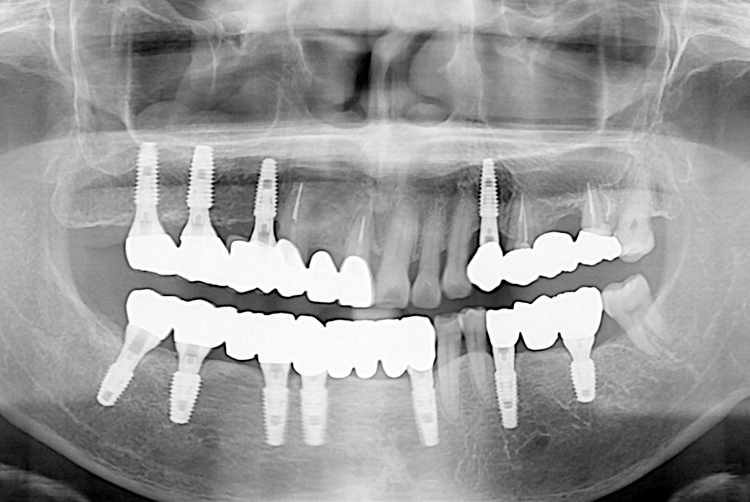

[임플란트] 임플란트

21.04.07.jpg

치료후 : 2021-04-07

세종치과는 많은 환자와 다양한 케이스를 바탕으로 항상 편안한 임플란트 수술을 제공하고자 노력하고,

오래동안 튼튼히 쓸 수 있는 임플란트 수술을 가장 큰 목표로 삼고 있습니다